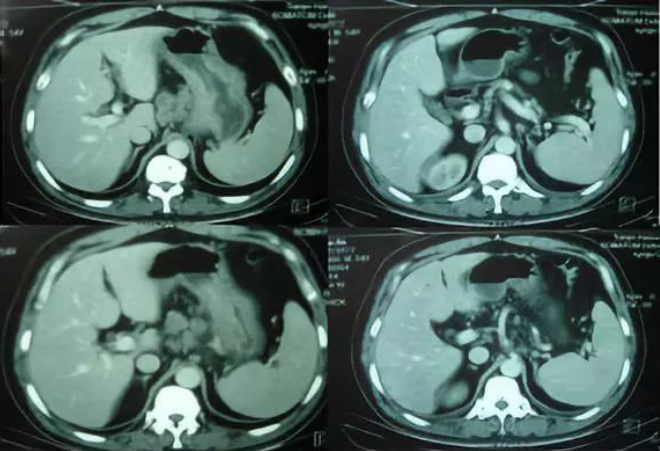

胃镜:进镜40cm见息肉样病变延及贲门及胃底、胃体,胃腔狭窄,尚能通过镜身,胃体中部近半周弥漫性粘膜破坏区,咬检病理(胃底)中分化腺癌,(贲门)粘膜急慢性炎症,腺体重度不典型增生,于炎性渗出及坏死组织中见异型细胞巢;HER2过表达,IHC 3+。肿标:CA199 742U/ml;CEA 78U/ml。胸腹盆CT:贲门胃底胃壁及胃体上部胃壁不规则增厚;下纵膈贲门周围肝胃韧带区及腹膜后多发肿大淋巴结;腹盆腔少量积液。

▲胸腹盆增强CT(2014.09.02)

小结:中年男性,探查术后患者,晚期胃癌诊断明确,肝门区,腹膜后多发转移。讨论目的:制定进一步治疗方案。

影像科:从目前CT考虑,贲门部肿瘤累及胃底胃壁,伴腹腔多发转移,分期明确。